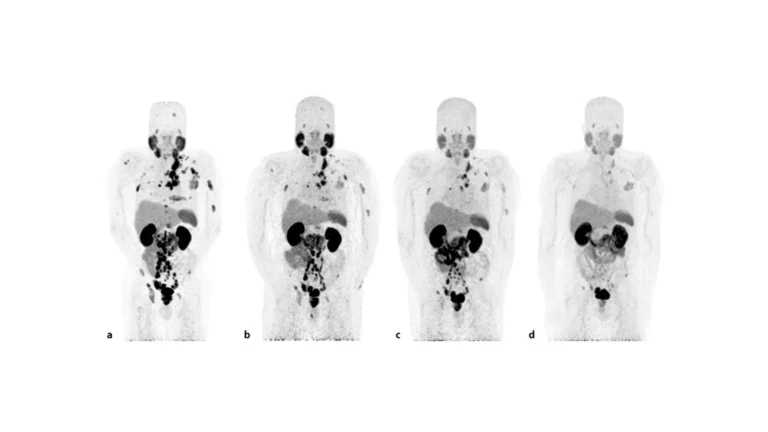

La teragnosis se posiciona como una de las innovaciones más prometedoras en el tratamiento oncológico actual. Esta...